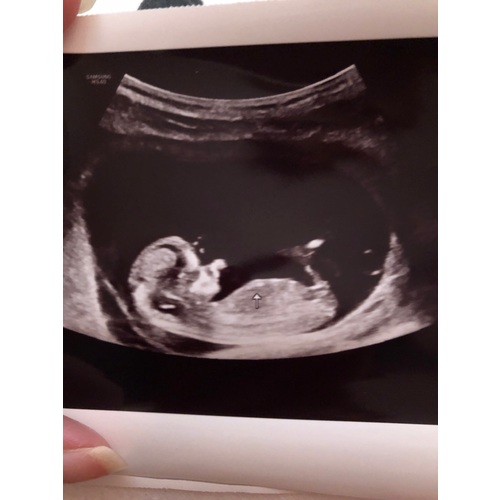

Wat denken jullie dames een meisje of een jongen 💖💙

12 weken en 1 dag. Iemand een idee jongen of meisje 🥰

12 weekjes

Ik neig naar jongetje. Had je nog een tweede foto toevallig?

We krijgen een meisje💗

Oh dan was toch de navelstreng boosdoener🙈 Zo zie je maar waarom een tweede foto zo handig kan zijn, je ziet vaak meer.